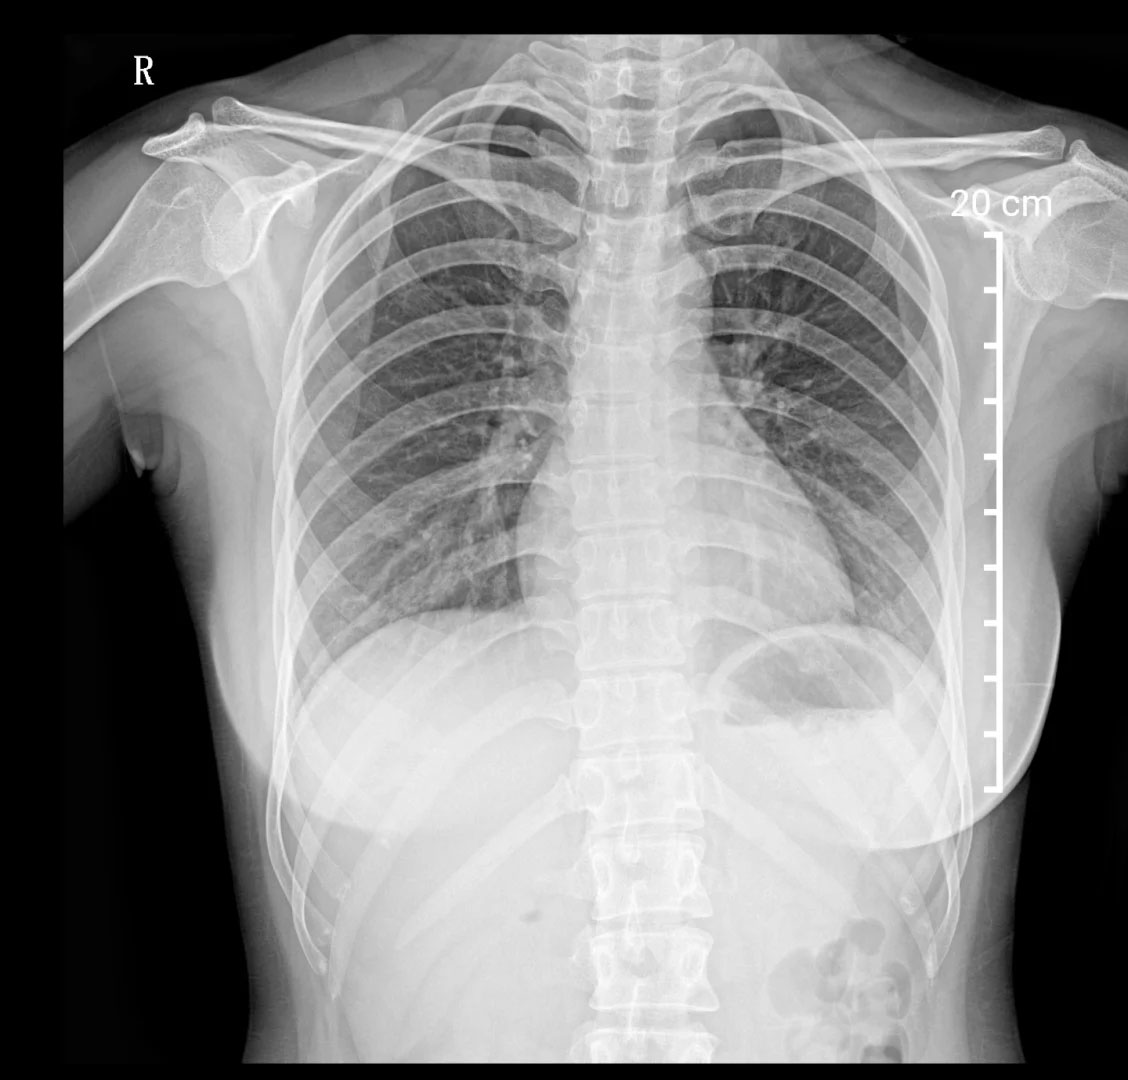

胸部X光檢查,建筑工地的環(huán)境復(fù)雜,肺部檢查很重要。有的工種需要長期接觸灰塵,可能會引起輕微肺部炎癥。在工地工作的時(shí)候,盡量要佩戴好口罩。